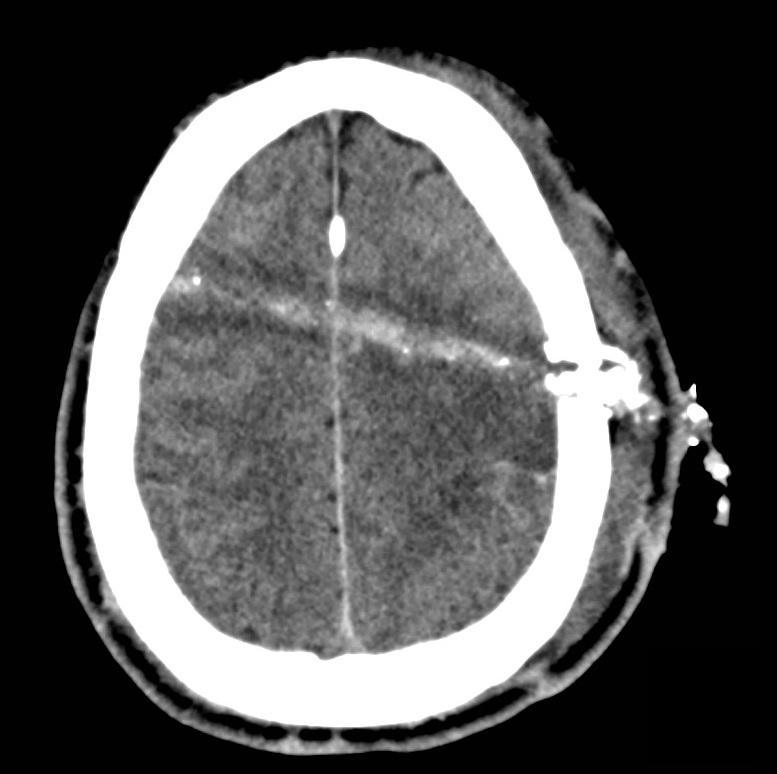

GSW Skull